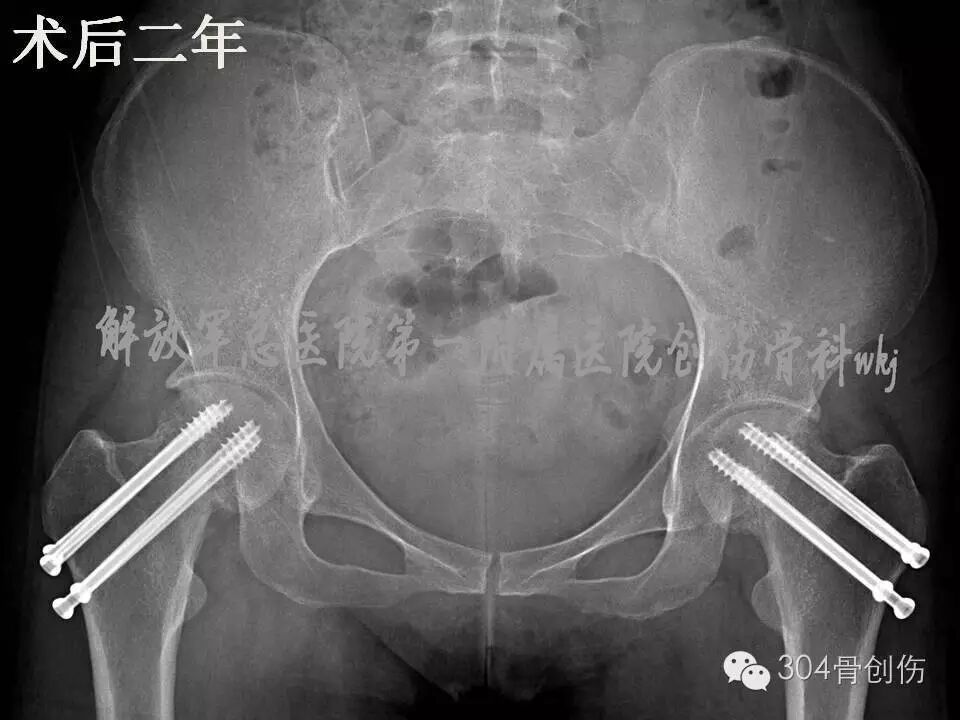

术后6个月患髋部X线显示,股骨颈有短缩,螺钉少许退钉,骨折基本愈合,骨折愈合左侧优于右侧。术后1年,股骨颈未继续缩短,左侧股骨颈完全愈合,右侧股骨颈略差,行走时右髋偶感不适。术后2年随访时(图),双侧股骨颈骨折愈合,患者步态正常(图)。

图-术后两年X线片